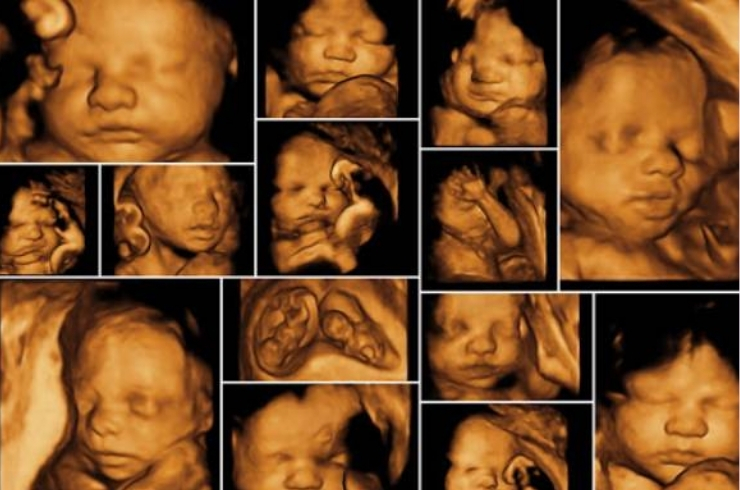

Advanced ultrasound providing detailed, real-time fetal images, enhancing visualization of baby’s features and movements during pregnancy.